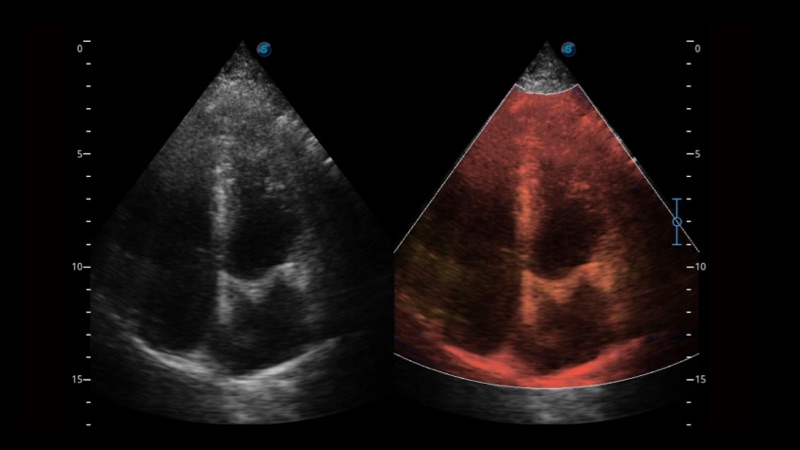

開立醫(yī)療通過不斷的技術(shù)創(chuàng)新,為大眾的生命健康提供持續(xù)關(guān)愛。P12 Plus采用全新一代超聲成像平臺(tái),新平臺(tái)旨在將真實(shí)還原組織解剖結(jié)構(gòu)作為首要目標(biāo)。平臺(tái)采用全新集成化硬件模塊,搭載新一代芯片,系統(tǒng)性能得到大幅提升,為您的診斷提供了豐富的臨床信息。優(yōu)異的圖像表現(xiàn),豐富的探頭配置,全面的應(yīng)用功能,為您日常診斷提供了可靠的助手。

P12 Plus

彩色多普勒超聲診斷系統(tǒng)